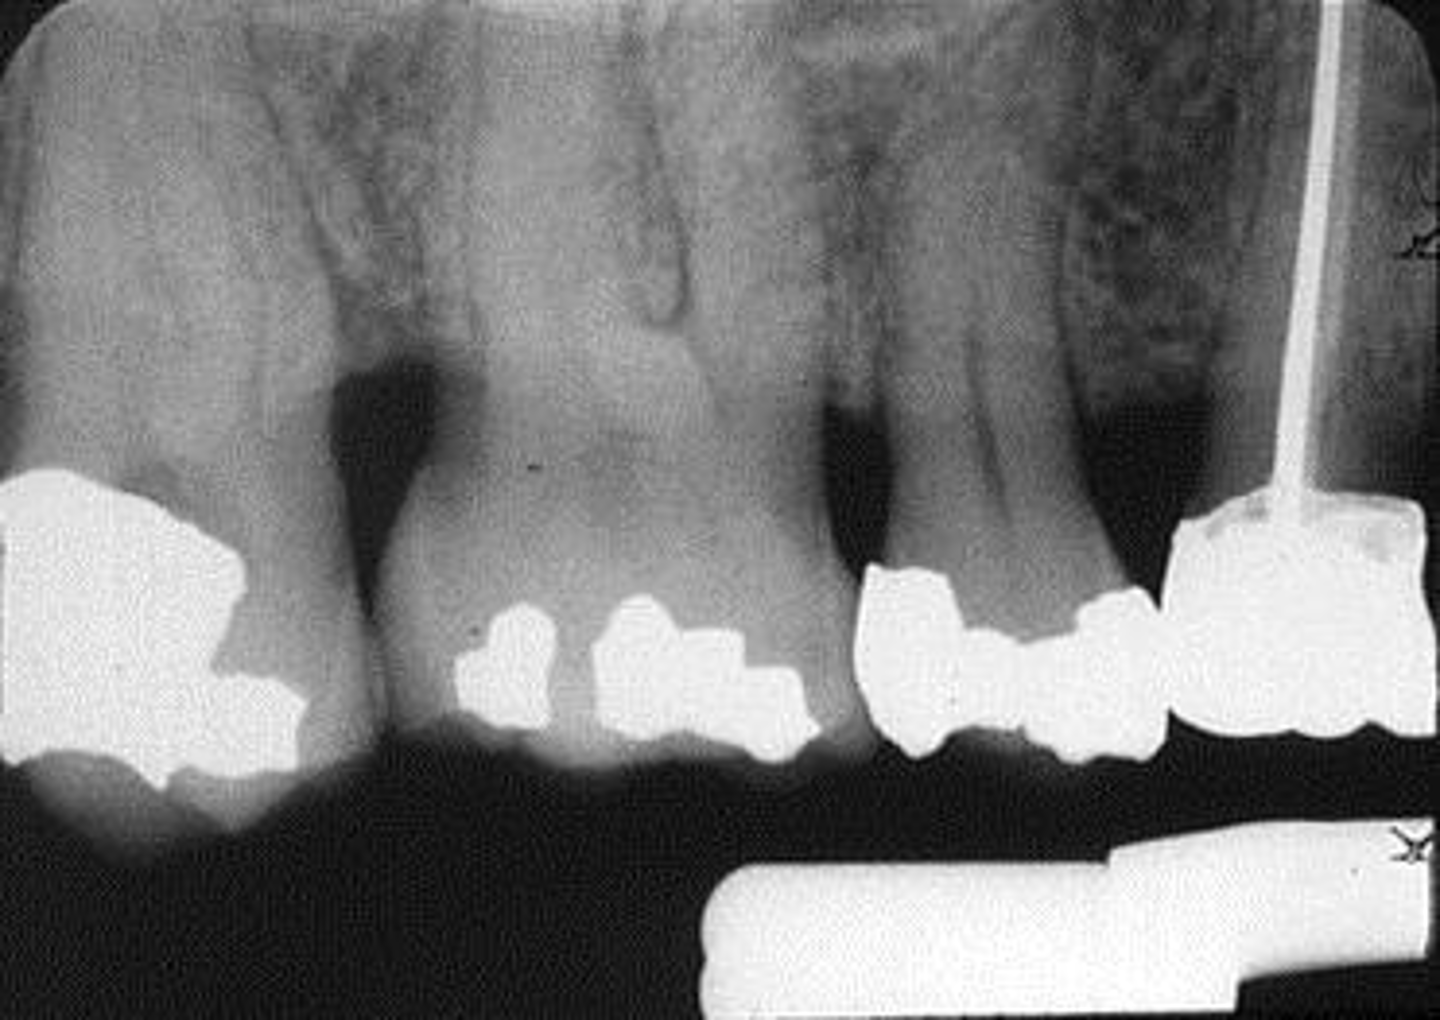

Elongated, vertical angulation, film holder (metal bar)

What is this error?